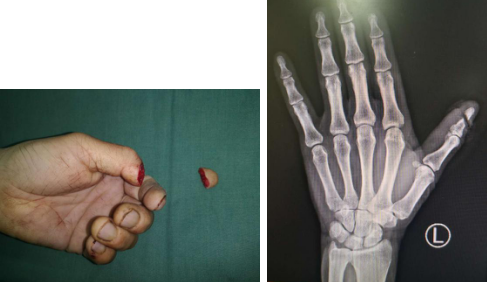

家住安徽的50岁丁先生(化名),一直以做木工活谋生,每年正月初七、八,他就会抓紧开工。但今年因为疫情的影响,他在家休息的时间格外长。当地逐渐解封后,闲了一个月的丁先生便抓紧时间进料开工了。2月22日下午,丁先生做完准备工作后开始了今年的第一单生意,当他用电锯去切割一块质地较为坚硬的木料时,手劲一弱,只见电锯突然反弹起来,然后快速旋转的锯片狠狠地砸在他的左手上,等他回过神来时发现左手拇指已经鲜血淋漓,一截拇指已经掉了下来。丁先生赶紧停了电锯,捡起断指,握紧伤口,大喊自己的妻子过来帮忙。

在妻子的陪同下,丁先生来到了betway在线登陆。正在值班的滕道练医师接诊后发现患者左拇指自指甲根部离断,断端因锯片的切割参差不齐,挫伤严重。滕医师抓紧时间为其包扎止血,办理住院手续,完善检查后送往手术室。在显微镜下滕医师发现丁先生的左拇指在手指动脉的末端汇合处(动脉弓)断裂,而且因为锯刃的宽度和摆动,可供吻合的血管长度大大缩短,几近末端且管径非常细小。滕医师将情况告知丁先生后,丁先生便慌了神,不住地请求滕医师帮他把手指接上去。滕医师安抚好丁先生,思索了一会后就制定了手术方案。首先缩短部分指骨以降低血管吻合的张力,骨折复位固定后,显微镜下仔细游离断裂的动脉,这一步极其困难,因为残留的血管无论长度和管径都极其细小,在这个断裂平面吻合的机会只有一次,一旦失败那么这例断指将无法完成再植。滕医师深吸一口气继续操作起来,15分钟后,断裂的动脉已全部吻合上了,松开血管夹看到吻合的血管膨胀搏动起来,滕医师长舒了一口气,一直紧绷的那根弦终于稍微放松了一些,手术顺利结束。